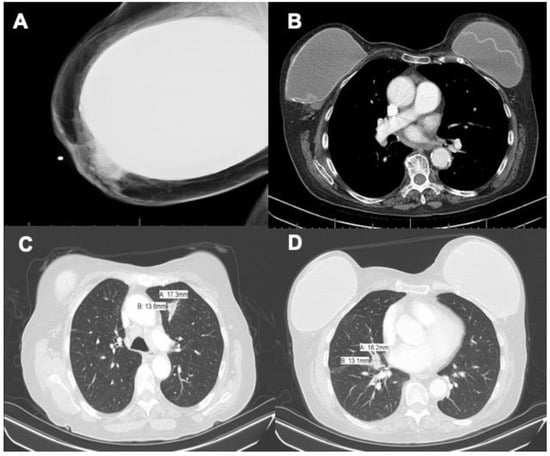

2. Case Presentation